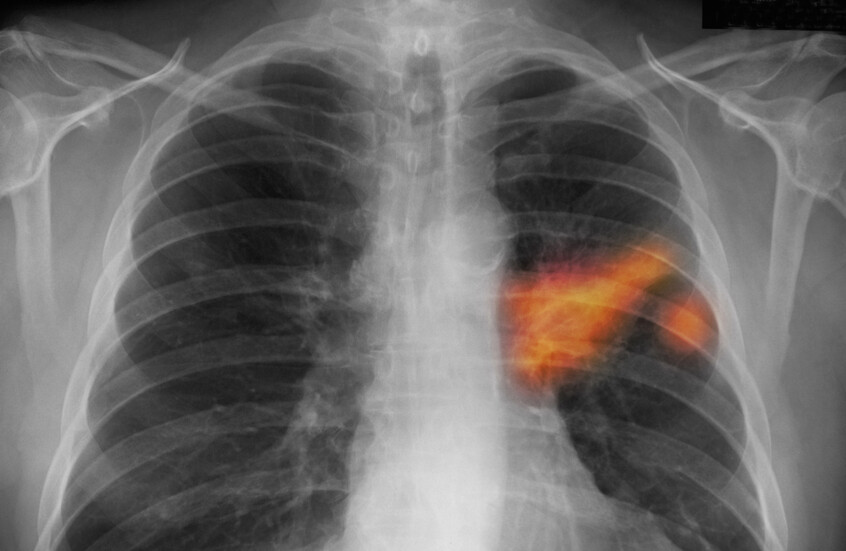

العلماء يحددون آلية تربط “كوفيد-19” بسرطان الرئة

كشفت دراسة دولية أن فيروس كورونا قد يترك آثارا صحية طويلة المدى تتجاوز المرحلة الحادة من المرض.

وتبين أن الفيروس قد يزيد قليلا من خطر الإصابة بسرطان الرئة، خاصة لدى المدخنين، وذلك من خلال سلسلة من التفاعلات البيولوجية التي يقودها بروتين “سبايك” الشهير.

ووجد الباحثون أن الناجين من “كوفيد-19” أظهروا زيادة طفيفة لكنها ملحوظة إحصائيا في خطر الإصابة بسرطان الرئة، حيث ارتفع الخطر النسبي بنسبة 22%. وكان هذا الخطر مرتفعا بشكل خاص بين المدخنين الحاليين.